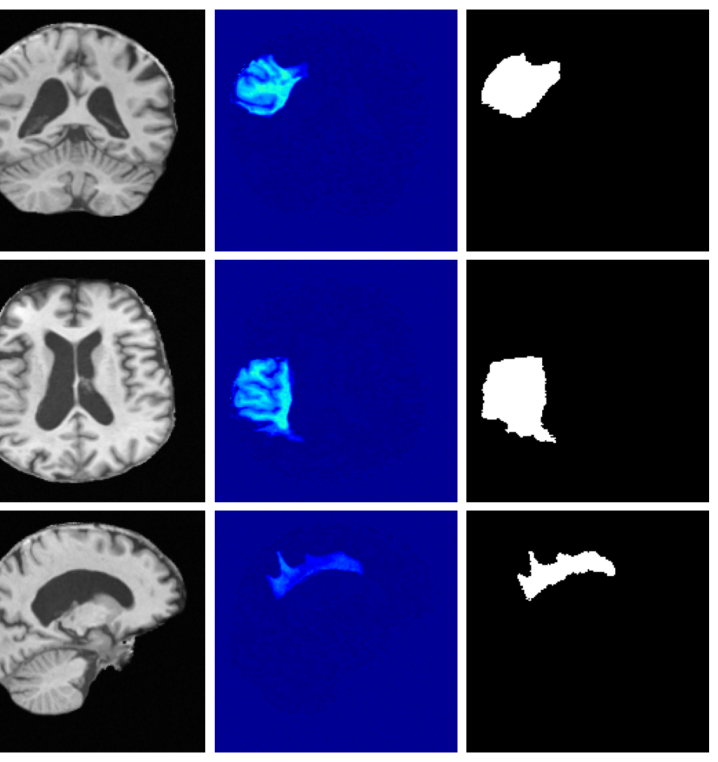

Inpainting. In some cases, we may wish to inpaint disease or corrupt regions of an image with realistic healthy tissue while preserving individual anatomical characteristics. This enables the use of a wide range of existing analysis tools that often fail or produce unreliable results in the presence of pathology. For such inpainting tasks, we can define the likelihood given a binary mask where indicates healthy pixels and indicates pathology pixels and defining a selection matrix where is the number of healthy pixels:

This formulation allows the prior to determine the values of disease regions while constraining healthy pixels to match the data.

4.3 Image inpainting results

Inpainting results are given in Table 3. Our method achieves the best overall performance, attaining the highest rank on both datasets. For ATLAS, our method outperforms all baselines with improvements of 39.2% (VAE), 8.3% (VAE), 2.7% (VAE), 44.2% (LDM), 19.0% (LDM), and 51.4% (LDM). On BraTS, it improves over the best baselines by 25.6% (VAE), 5.2% (VAE), 27.4% (LDM), and 15.2% (LDM), while remaining competitive on the remaining metrics.

Figure 3 (additional examples in Appendix A.9) shows that SynthSR preserves healthy tissue but struggles with large lesions, while DDPM-2D and DDPM-3D, despite producing high-contrast anomaly maps, generate unrealistic homogeneous inpainting, consistent with their lower performance in Table 3. In contrast, our method yields the most anatomically plausible inpainted regions, although anomaly maps appear subtle due to low contrast between lesions and healthy tissue.